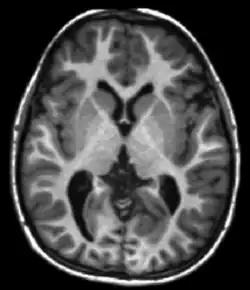

T1 and T2

Each tissue returns to its equilibrium state after excitation by the independent relaxation processes of T1 (spin-lattice; that is, magnetization in the same direction as the static magnetic field) and T2 (spin-spin; transverse to the static magnetic field). To create a T1-weighted image, magnetization is allowed to recover before measuring the MR signal by changing the repetition time (TR). This image weighting is useful for assessing the cerebral cortex, identifying fatty tissue, characterizing focal liver lesions, and in general, obtaining morphological information, as well as for post-contrast imaging. To create a T2-weighted image, magnetization is allowed to decay before measuring the MR signal by changing the echo time (TE). This image weighting is useful for detecting edema and inflammation, revealing white matter lesions, and assessing zonal anatomy in the prostate and uterus.

The standard display of MRI images is to represent fluid characteristics in black and white images, where different tissues turn out as follows: